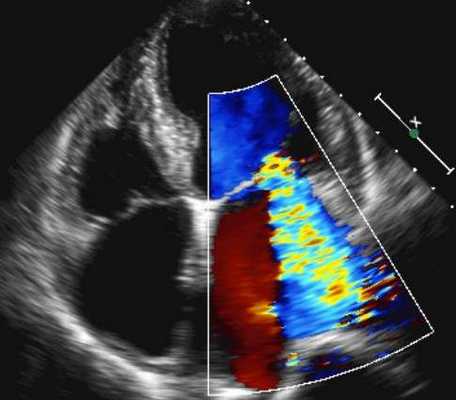

Цветной допплер при легочной гипертензии

• Следующие параметры на эхокардиографии соответствуют тяжелой регургитации на трехстворчатом клапане:

- Радиус площади проксимальной поверхности (PISA) 10,6 мм для предела Найквиста 28 см/с.

- Радиус PISA 6,8 мм для ограничения Найквиста 41 см/сек.

- Струя площадью 10,6 см2.

- Струя длиной 5,3 см.

- Отношение струи к правой предсердности> 40%.

- Ширина вены контракта составляет ≥6,5 мм.

• Точная оценка степени тяжести ТР по эхокардиографии требует интеграции доплеровских параметров с параметрами давления ЛА, размерами и функции правого желудочка, а также размера и давления в правом предсердии.